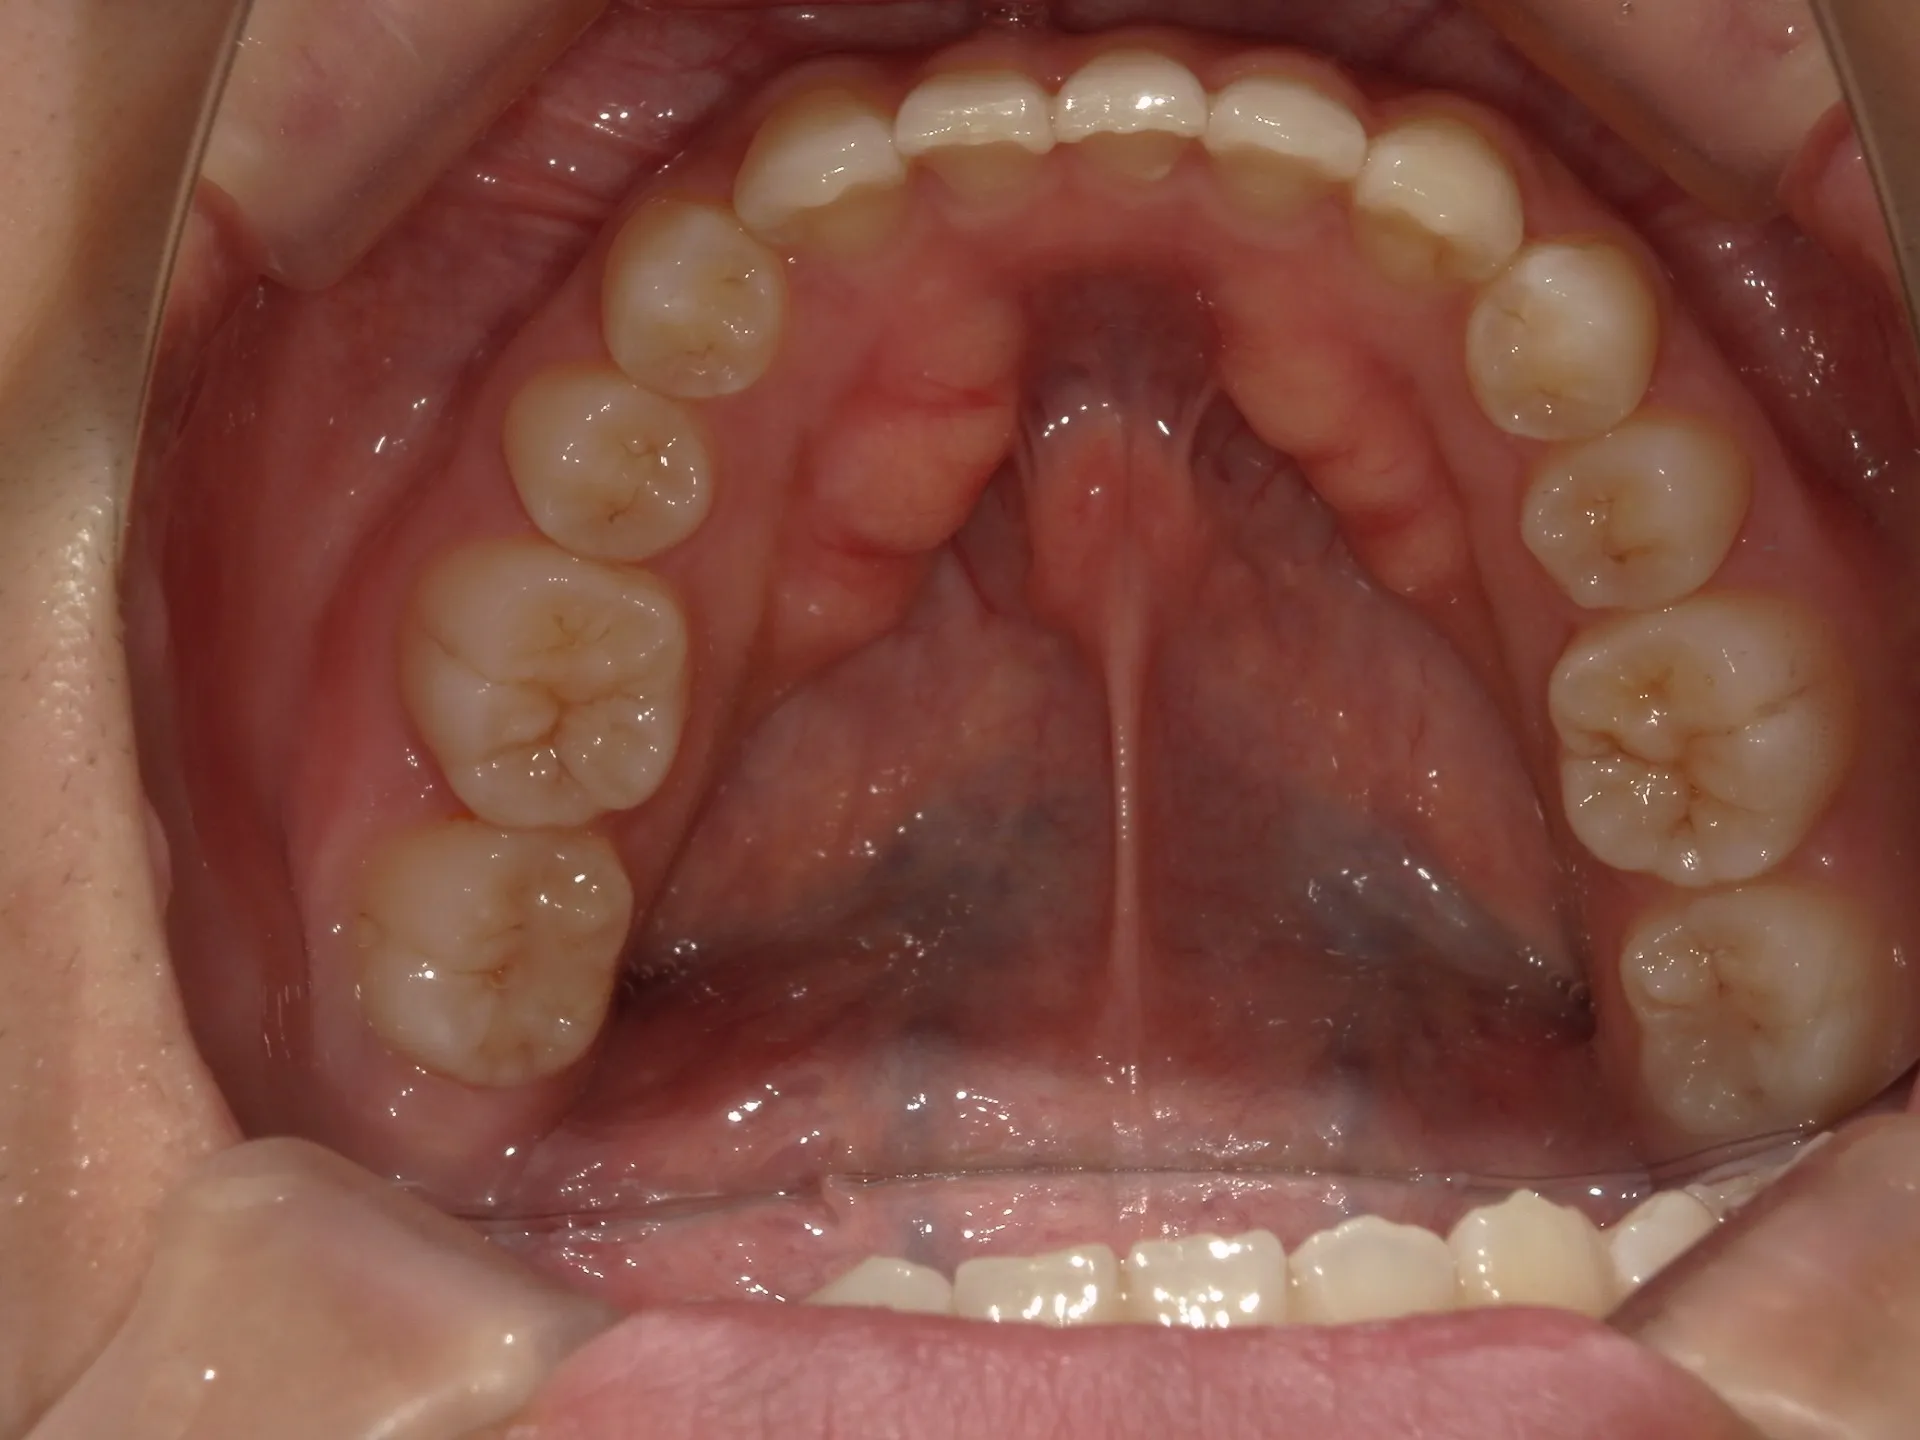

前歯が内側に倒れてたりしませんか?

または2番目の歯が外側に飛び出していませんか?

この2つはよく同時に起こることがあります。

今回はインビザライン矯正治療(マウスピース矯正)で治療した症例についてご紹介いたします。